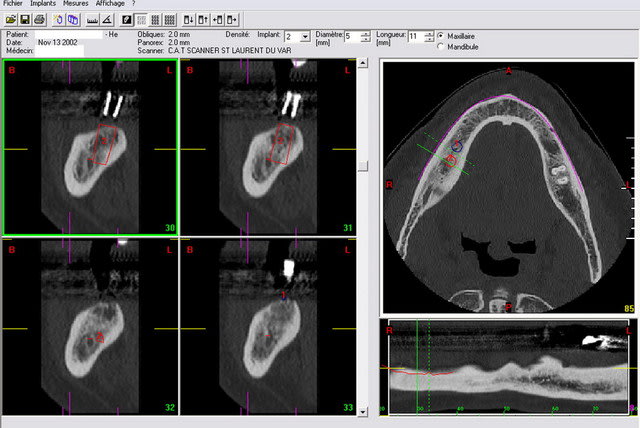

Je t'envoie 3 images de dentascan avec sur la premiere une "mesure" telle que tu l'aurais eu avec une retro-alveolaire sans deformation. On trouve 11,2 mm et une crete tres large favorable à un implant de diametre 5 mm et donc de longueur 1O ou 11 mm maxi.

Seconde image avec la simulation d'un implant de 11 mm... On est dedans ou alors on traverse la corticale linguale. Et encore ds cet exemple la corticale linguale ne fait pas un tres gros décroché comme on peut le voir parfois.